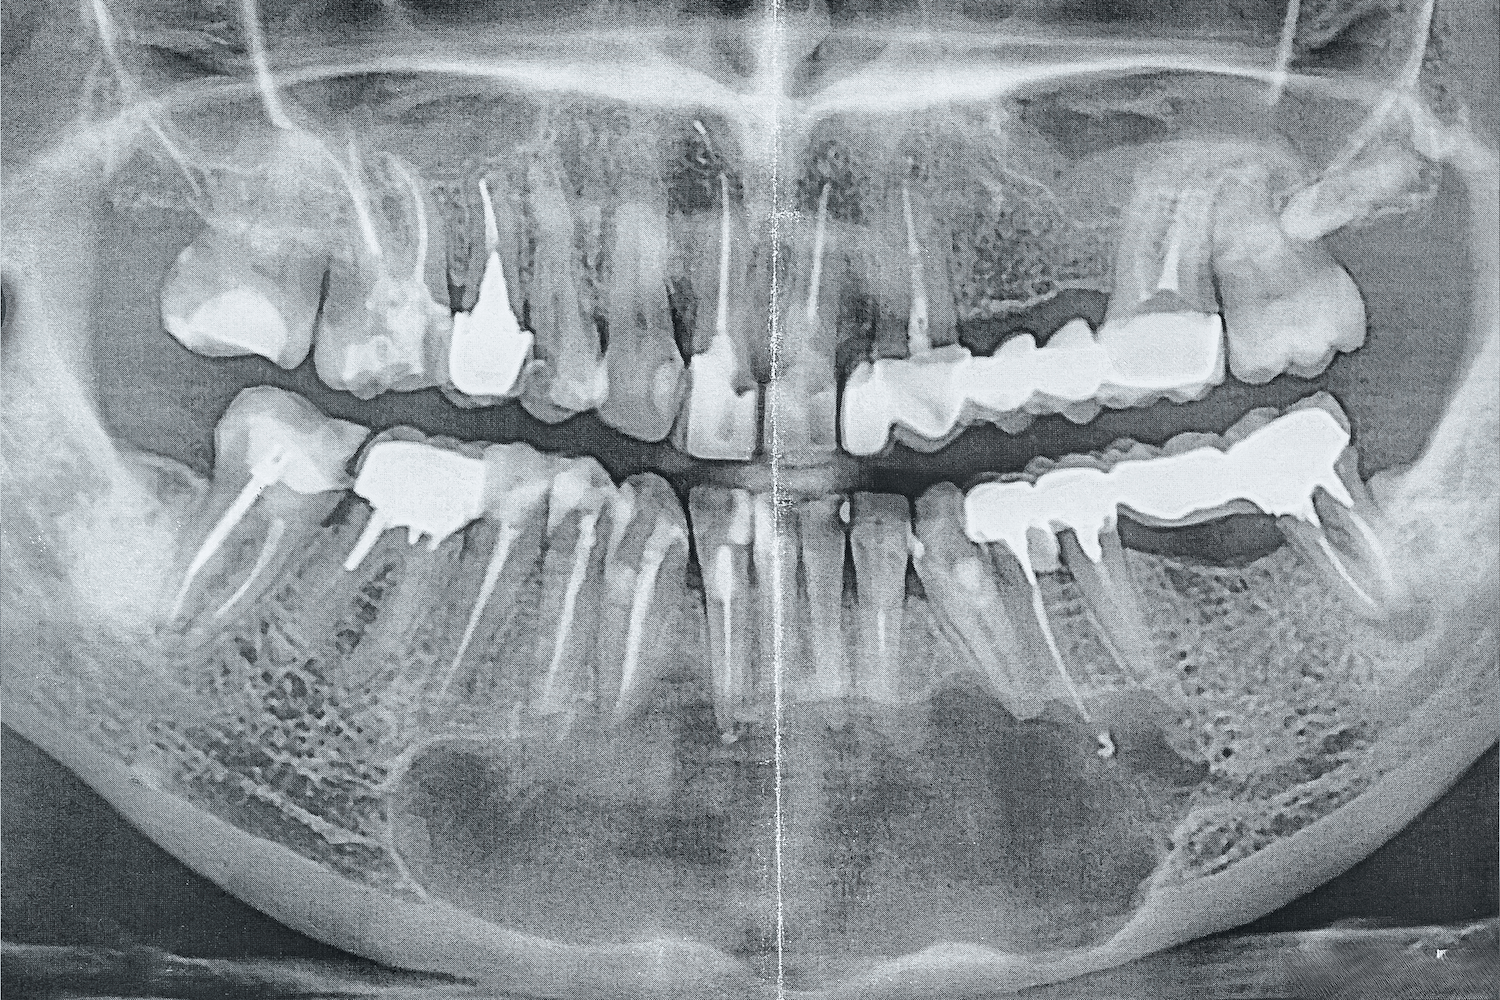

Около десяти лет назад к нашему врачу Максиму Макаренко обратилась пациентка с целью получить альтернативное мнение врача. Во время диагностики на панорамном снимке врач обнаружил интактные (здоровые) зубы на нижней челюсти и в области подбородка, в области апексов фронтальных зубов кисту с четким очертанием. Киста была достаточно большого размера, а именно от зуба 4.5 до зуба 3.5. То есть почти все зубы нижней челюсти были поражены новообразованием.

Дополнительно пациентку беспокоило онемение губы с обеих сторон, низа подбородка (из-за давления кисты на выход нерва из ментального отверстия).

После осмотра, изучения ОПТГ-снимка и выслушав жалобы пациентки, врач обнаружил зуб, вызвавший образование кисты (зуб 3.2) и предложил лечение, которое позволит сохранить все зубы. Пациентка согласилась на лечение, состоявшее из следующих этапов: